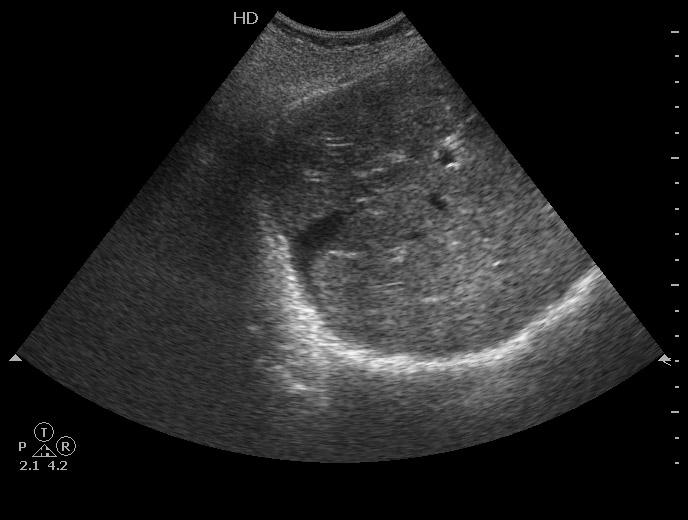

Все верно, разрыв печени плюс жидкость в боковом синусе плевральной полости.

Ультразвуковая семиотика разрыва довольно типична. Разместить эту сонограмму решил после того, как увидел протокол из одной авторитетной клиники, где гемангиома была трактована как разрыв печени и внутрипеченочная гематома.

Добавлю еще пару случаев

Краевой разрыв с гемоперитонеумом (вне поля сканирования)